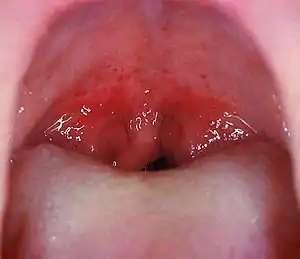

Angines

Ce sont de loin les plus fréquentes conséquences des streptocoques hémolytiques. Environ 45 % des angines rouges et pultacées sont dues à ces streptocoques (l'étiologie des autres angines est virale dans 45 % des cas, celle des 10 % restants est due à des germes divers: diphtérie, staphylocoques, haemophilus, association fuso-spirillaire de Vincent, monilias et mycoplasmas).

- Le Streptococcus pyogenes, du groupe A de Lancefield, est à l’origine d'une forme minoritaire d’angines rouges (la majorité est d'origine virale), d’infections cutanées (impétigo), d’abcès, d’infections broncho-pulmonaires… Les angines à streptocoque A peuvent être associées à la scarlatine : elles peuvent également évoluer vers des complications comme le rhumatisme articulaire aigu (RAA) si la maladie n’a pas été traitée étant jeune.